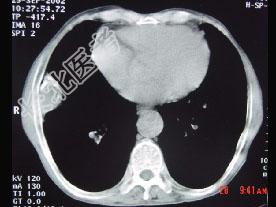

- 单项选择题CT图像,最可能诊断为 ( )

A、右肺肺占位

B、右侧胸膜良性病变

C、肋骨病变侵犯胸壁

D、膈膨升

E、纵隔肿块